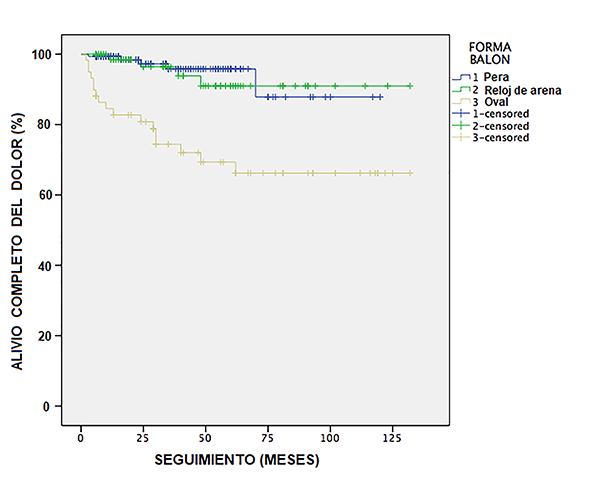

Los datos fueron ingresados en Microsoft Excel version15.26, luego transferidos al programa SPSS versión 22 donde fueron analizados. Se hizo primero un análisis descriptivo de las principales características de los pacientes operados, luego se realizó un análisis de sobrevivencia donde el evento fue la recidiva. Primero se usó el método Kaplan- Meier con la finalidad de comparar el porcentaje de recurrencia de la neuralgia del trigémino entre los tres tipos de balón observados en la cirugía: pera, en reloj de arena, u oval (Figura 9).

Figura 9: Curva de evaluación de Kaplan-Meier mostrando los resultados clínicos de 262 pacientes que se sometieron con éxito a compresión percutánea del ganglio de Gasser y raíz trigeminal con balón, diferenciando los resultados según la forma de balón.

Se observó recidiva del dolor en 26 pacientes (9.2%) con un tiempo de seguimiento de 6 meses a 11 años (promedio 5.75 años). La forma de balón oval tuvo la mayor tasa de recurrencia (65.4%) con respecto a los balones tipo pera o reloj de arena (Tabla 8). Esta diferencia fue significativa (p<0.001) usando la prueba estadística Logrank. No hubo diferencia significativa en cuanto a recidivas entre los balones tipo pera y reloj de arena.

La mayoría de los autores han enfatizado la obtención de una forma de pera del balón insuflado, y más recientemente también se ha demostrado que la forma de la pera es el factor más importante relacionado con la obtención de un resultado satisfactorio.16,17

Asplund y colegas demuestran que la forma del balón tuvo un impacto significativo en el tiempo de recurrencia del dolor. Un balón en forma de pera tuvo mejores resultados que un balón sin forma de pera (p <0.001). Se debe mencionar que en su serie no refiere ningún caso de balón en forma de reloj arena. La diferencia de sus resultados entre un balón de forma de pera y uno con forma menos clara de pera, “pera like” (com protuberancia hacia el poro trigeminal mínima o muy pequeña) no fue significativa (p = 0.14).16

En nuestros casos con balón en forma de pera tuvieron 95% de alivio completo del dolor, con reloj de arena 97.3% y con la forma oval 63.8%.

En nuestra serie las formas de balón tipo pera o de reloj de arena tienen una mayor probabilidad de alivio completo del dolor y menor recidiva comparada con la forma oval.